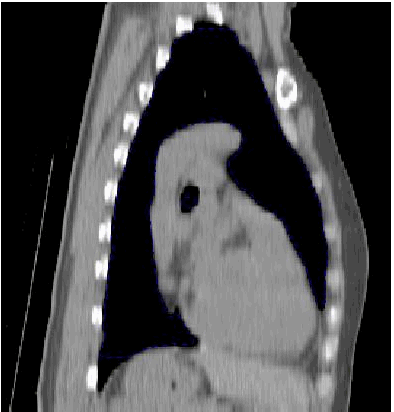

In der sagittalen Ebene ist die Distanzierung des Herzens von der Brustwand gut zu erkennen.